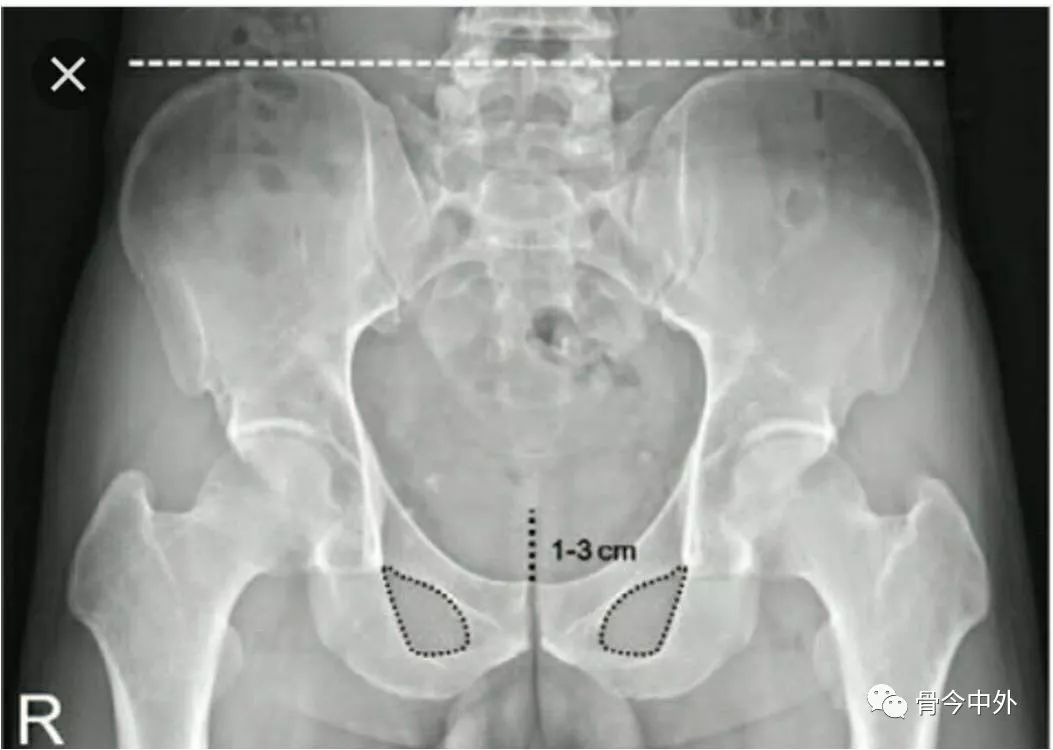

闭孔上缘与股骨颈内下缘连线(正常:平滑曲线)

Shenton线:又叫做兴登线、沈通氏线,是指成人髋关节正位片上,闭孔上缘与股骨颈内下缘连线,正常应为平滑曲线,若不连续提示髋关节脱位或者股骨颈错位骨折。

髂前下棘下方与股骨颈外侧缘连线(正常:平滑曲线)

Calve线:即髂颈线,髋关节正位片上,髂前下棘下方髂骨外缘级股骨颈外缘连线,正常为光滑曲线,若不连续提示髋关节脱位或者股骨颈错位骨折。